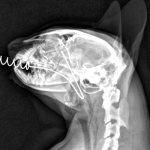

It is possible to identify the disease only through an external examination of the animal. But to get ahead of the location of the infection, biomicroscopy is used. If purulent keratitis is detected, then bacteriological tests are taken to find out the source of the disease. Fluorescent strips are used to determine the stage of the lesion and light sensitivity.

The veterinarian will examine the corneal tissue under a microscope to see if it is damaged or if there are any viruses causing irritation. A culture test will be performed. The condition of both eyes is analyzed for the degree of damage to the corneal tissue. The veterinarian will also determine how the treatment is progressing, whether the condition is improving or whether therapy still needs to be continued.